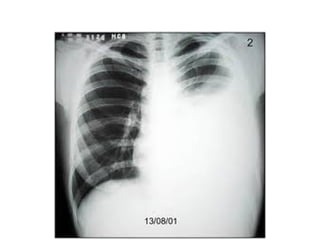

DERRAME LIBRE

• Se produce una sombra de la misma densidad del corazon,

que se localiza inicialmente en el angulo costofrenico

posterior, tiene concavidad superior siendo mas alta en la

region lateral que medial

• Para obliterar los angulos costofrenicos posterior y lateral se

requieren 75 y 175 ml de liquido respectivamente